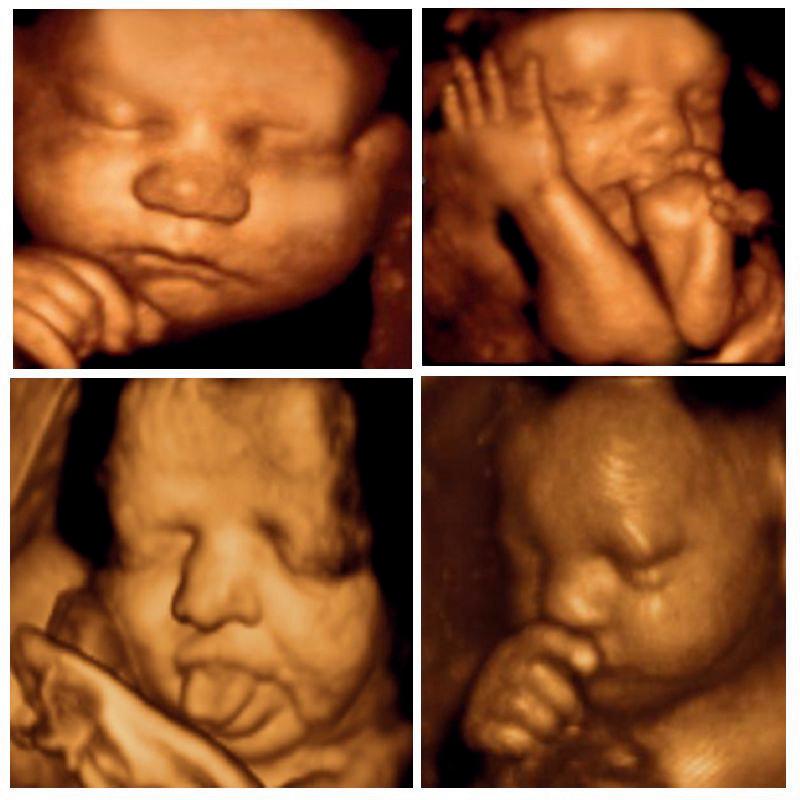

Birth